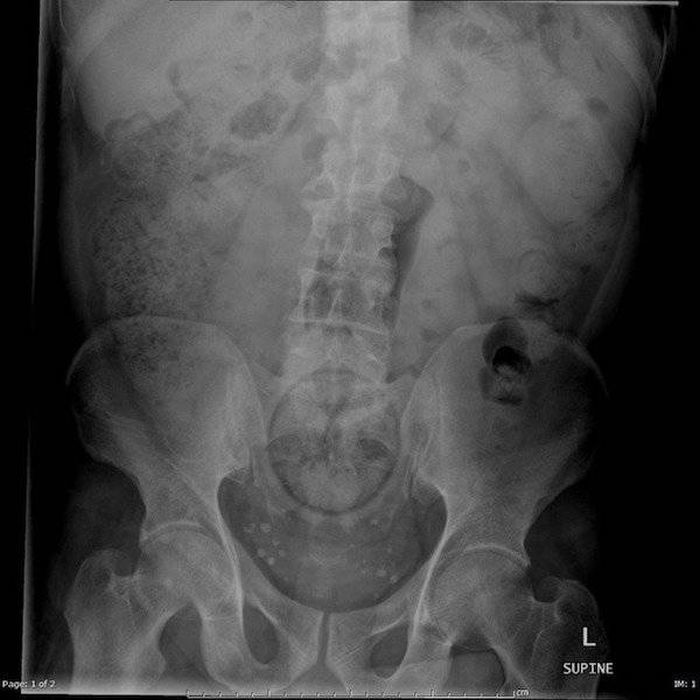

Предметы, которые не очень хочется видеть внутри себя

Под рентгеновскими лучами порой видны не только внутренние органы и кости, но и инородные тела, попавшие в организм

Истории попадания этих предметов в организм могут быть самыми невероятными и запутанными, но больше всего медиков интересует процесс их извлечения, впрочем, в этом заинтересованы и сами пациенты, допустившие нечто подобное со своим телом.